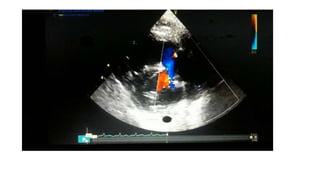

Echocardiography remains the gold standard

diagnostic tool in PPHN. A R-L shunting of blood

at the foramen ovale and/or the ductus

arteriosus , TR or a bowing of ventricular

septum to the left, to evaluate ventricular

function and to exclude CHD (e.g. infra

diaphragmatic TAPVR, HLHS). Ref: Jayasree Nair

et al. 2015

Echocardiography remains thegold standard diagnostic tool in PPHN. A R-L shunting of blood at the foramen ovale and/or the ductus arteriosus , TR or a bowing of ventricular septum to the left, to evaluate ventricular function and to exclude CHD (e.g. infra diaphragmatic TAPVR, HLHS). Ref: Jayasree Nair et al. 2015